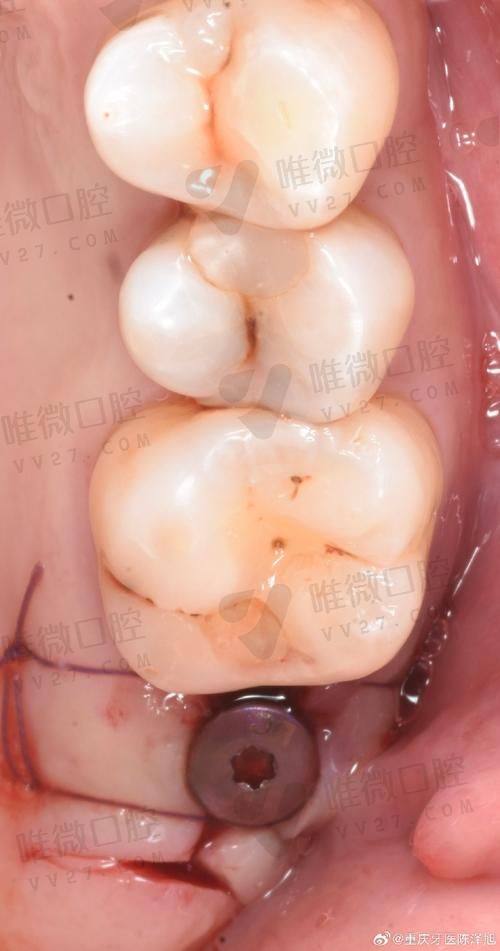

项目优势在于种植和正畸,医生技术稳定,而且价格合理:韩国登腾种植牙含冠仅从3680元起,相比市面动辄8000多的价格确实亲民不少。

技术倾向于微创与数字导航种植ALL-on-4方案,部分复杂病例推荐提前在此诊断探讨。